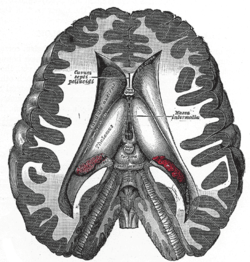

The four cavities of the human brain are called ventricles.[1] The two largest are the lateral ventricles in the cerebrum; the third ventricle is in the diencephalon of the forebrain between the right and left thalamus; and the fourth ventricle is located at the back of the pons and upper half of the medulla oblongata of the hindbrain. The ventricles are concerned with the production and circulation of cerebrospinal fluid[2]